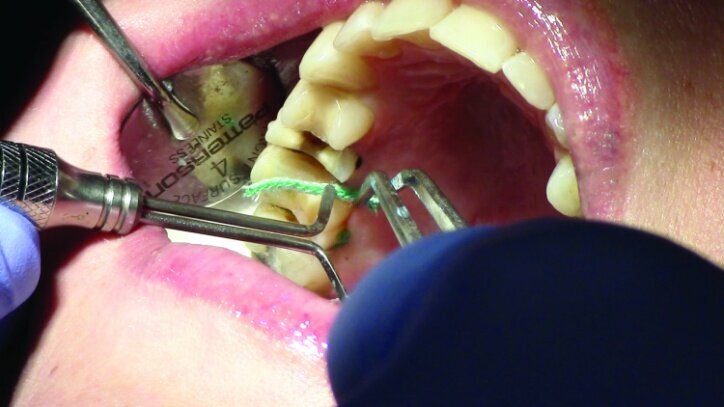

Tissue management was obtained with ViscoStat Clear, gingival haemostatic gel, 25 percent (m/m) aluminum chloride (Figs. 16 & 17). Gingival retraction was obtained using a two-cord system. First, a #00 size cord from Ultradent was placed on the mesial and distal of both preparations (Figs. 18 & 19).

Additional haemostatic gel was used prior to the second cord. The second cord was #2 size cord from Ultradent (Figs. 20 & 21a). A minimum of four minutes with both cords in place is needed for adequate retraction of the soft tissue (Fig. 21b).